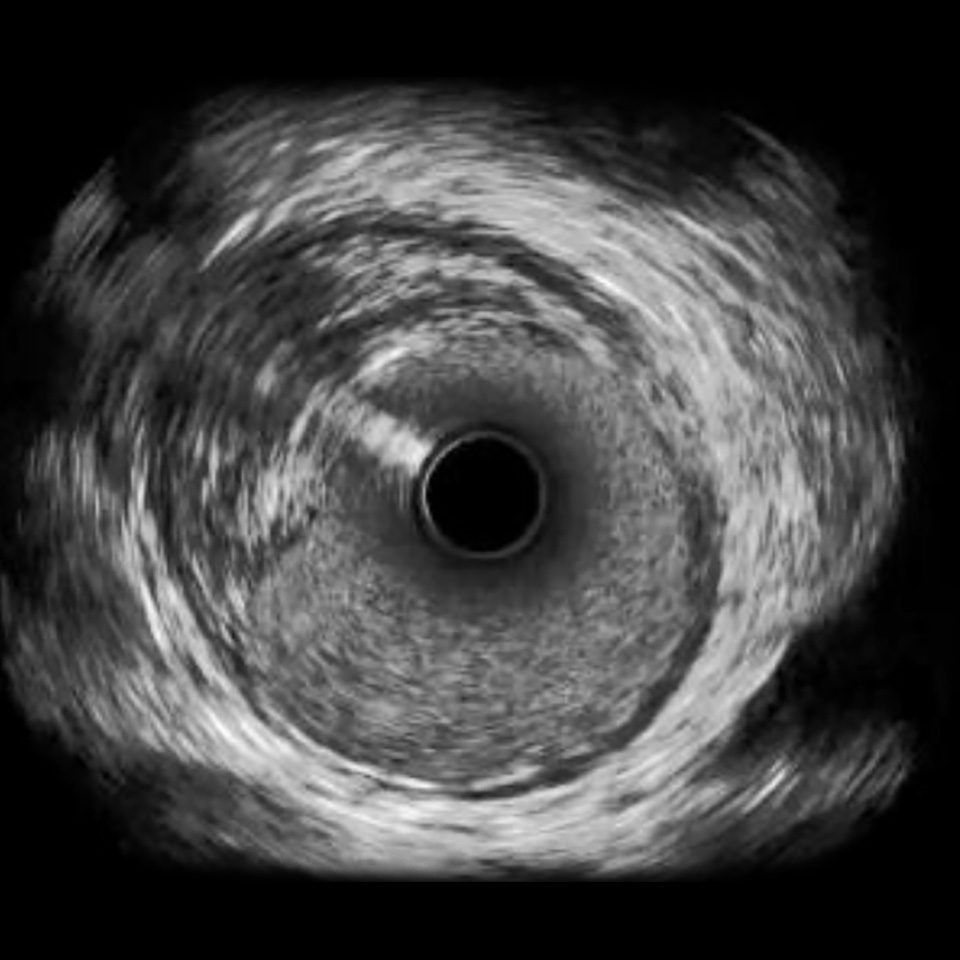

Philips Volcano Eagle Eye Platinum Imaging Catheter 20MHz

IVUS image of inside a coronary vessel using the 20MHz Philips Volcano Eagle Eye Platinum catheter

Axial resolution: <170 µm

High-Definition IVUS image quality helps physicians more accurately identify lesion length, assess plaque morphology, and determine the tools required for vessel prep. See how OPTICROSS HD’s 60 MHz images stack up against the competition.